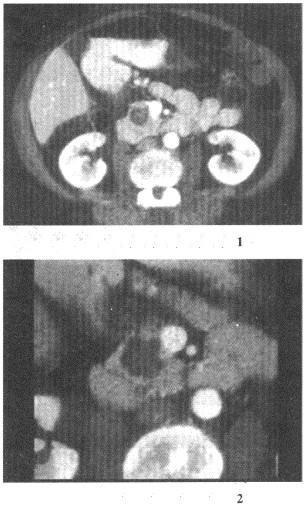

女,57岁,上腹部隐痛半年余,CT检查如图![]() |

| 12.最可能的诊断是 |

| 正确答案:12.D;13.A;14.A 解题思路:可见增强扫描肿块内呈蜂窝状结构,为胰腺囊腺瘤的特点。 |